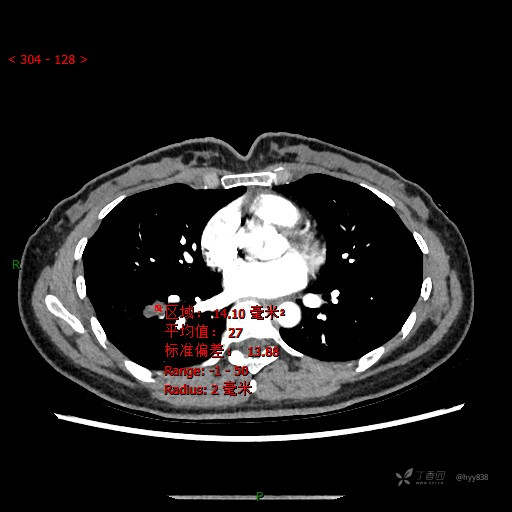

胸部CT平扫

CT值